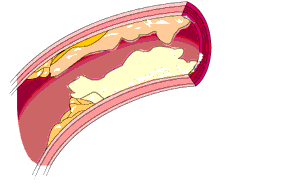

➤1977年——在心血管造影技术的基础上,发明了PTCA术(冠状动脉球囊扩张术)。

PTCA术

在狭窄的冠状动脉处放置一个球囊,经过它的扩张,让狭窄的血管重新变“粗”,血流可以通畅地经过狭窄的血管供应到心脏的其他部分。

因为在一部分病人中,PTCA术的球囊扩张以后,当把球囊拿掉时,血管又重新“狭窄”回来了。如果在局部放一个支架,把血管“顶住”,就能不让血管重新“狭窄回来”。